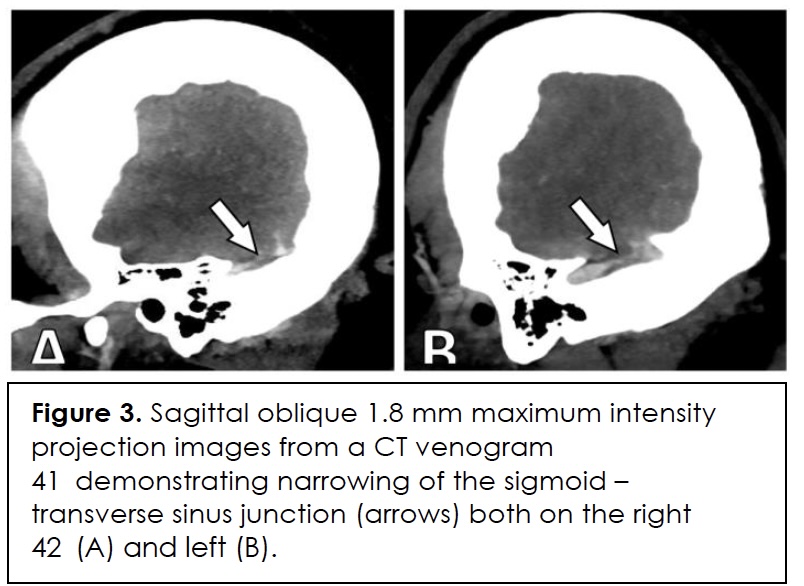

In this case, diagnostic specificity was also undermined by the patient’s simultaneous risk factors for infection and immunosuppression such as type 2 diabetes, obesity, recent adrenalectomy, and corticosteroid therapy. Her migraine history and probable idiopathic intracranial hypertension without papilledema (IIHWOP) initially predisposed towards a primary headache diagnosis. Brain imaging ruled out an intracranial mass, and she met two radiographic criteria for IIHWOP – empty sella (Figure 2) and transverse sinus narrowing (Figure 3) – that are consistent with the modified Friedman criteria for diagnosis 8. However, inability to demonstrate papilledema and absence of a persistent response to therapy prompted further investigation.